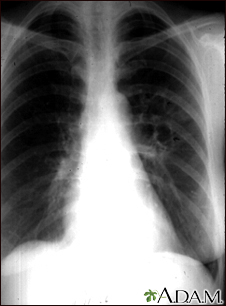

Coccidioidomycosis - chest x-ray